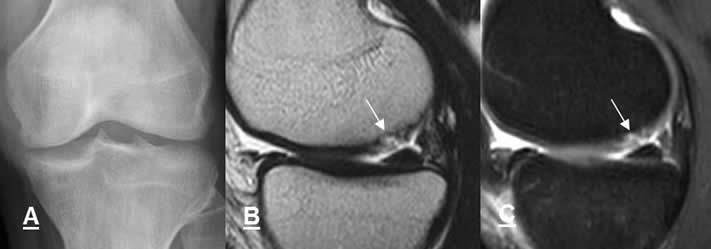

Fig 23 C. Lesión condral.

A: Rx AP. No se encuentran alteraciones.

B: RM sagital en T2 y C: RM sagital en STIR. Defecto en el cartílago sobre el borde inferior del cóndilo femoral medial, por desprendimiento condral.